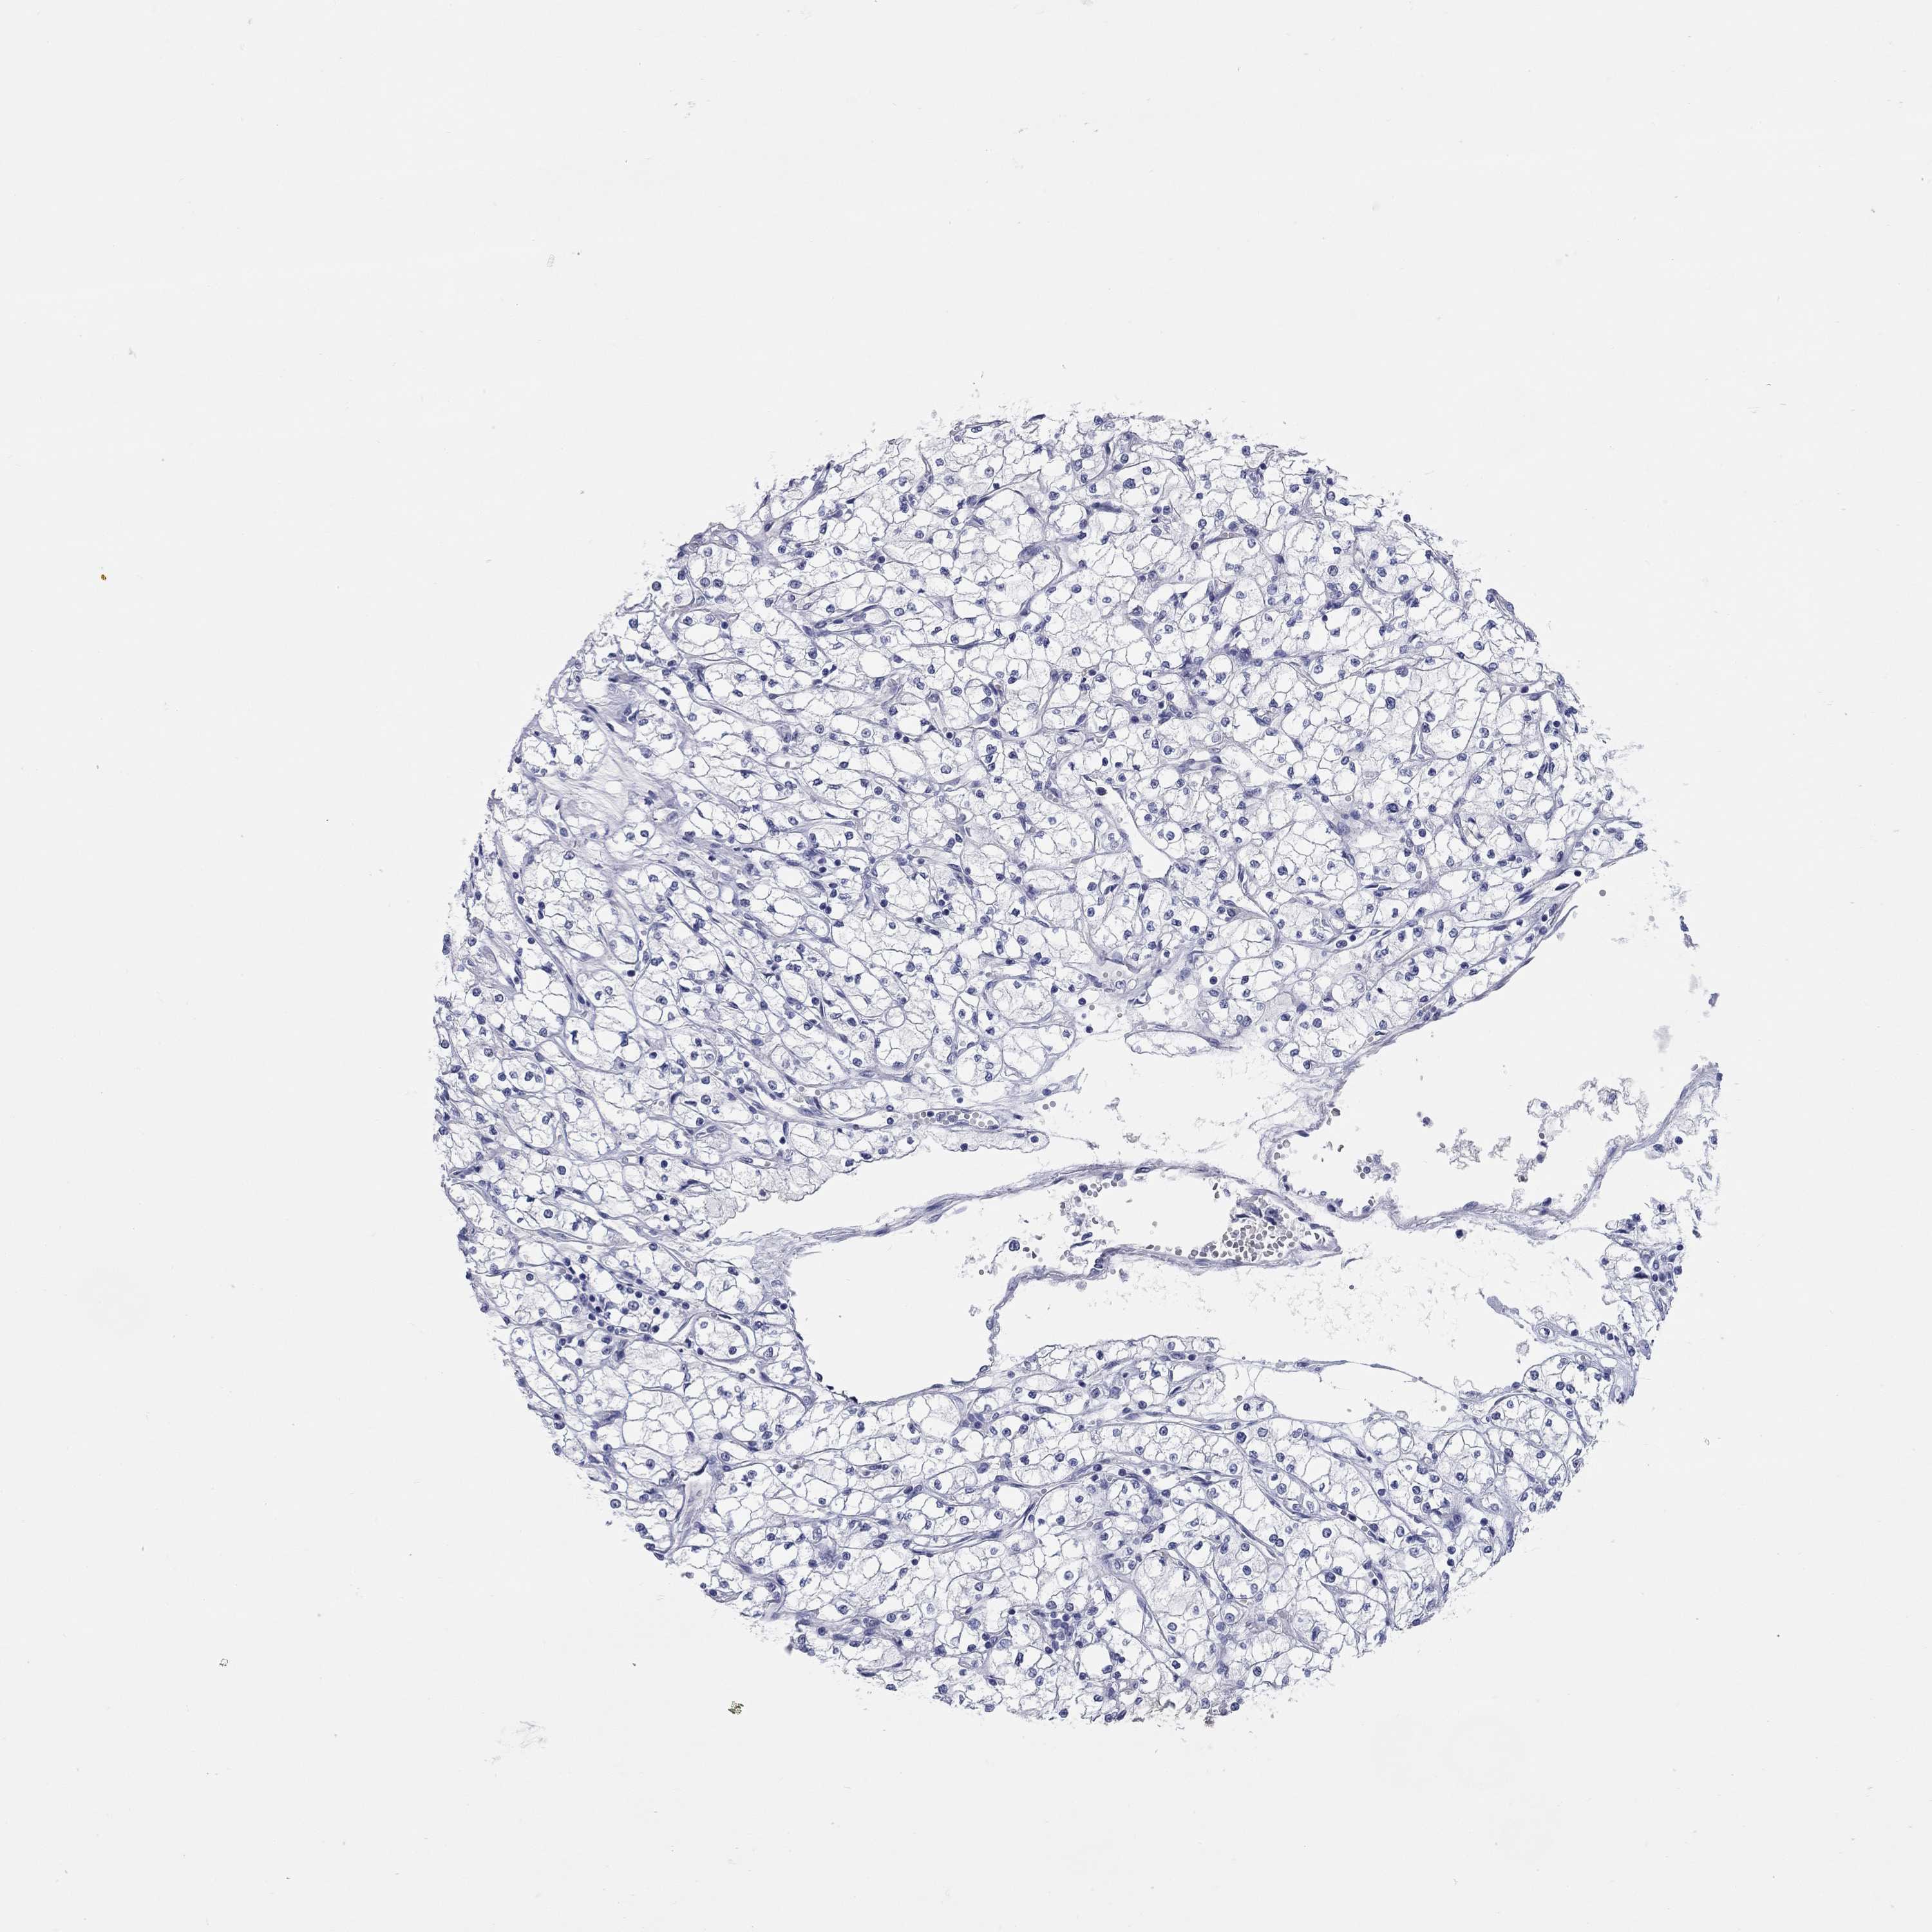

KIDNEY RENAL CLEAR CELL CARCINOMA (TCGA) - Interactive survival scatter ploti

The Survival Scatter plot shows the clinical status (i.e. dead or alive) for all individuals in the patient cohort, based on the same data that underlies the corresponding Kaplan-Meier plots. Patients that are alive at last time for follow-up are shown in blue and patients who have died during the study are shown in red.

The x-axis shows the expression levels (FPKM) of the investigated gene in the tumor tissue at the time of diagnosis. The y-axis shows the follow-up time after diagnosis (years). Both axes are complimented with kernel density curves demonstrating the data density over the axes. The top density plot shows the expression levels (FPKM) distribution among dead (red) and alive patients (blue). The right density plot shows the data density of the survived years of dead patients with high and low expression levels respectively, stratified using the cutoff indicated by the vertical dashed line through the Survival Scatter plot. This cutoff is automatically defined based on the FPKM cutoff that minimizes the p-score. The cutoff can be changed by dragging the vertical line or by entering a cutoff value in the square labeled "Current cut-off".

Under the Survival Scatter plot the p-score landscape (black curve; left axis) is shown together with dead median separation (red curve; right axis). Dead median separation is the difference in median mRNA expression between patients who have died with high and low expression, respectively. It is calculated as follows: median FPKM expression of dead patients with high expression - median FPKM expression of dead patients with low expression. This is intended to aid the user in visually exploring custom cutoffs and the associated p-scores and dead median separation.

Individual patient data is displayed and can be filtered by clicking on one or more of the category buttons on the top of the page. Categories describing expression level and patient information include: high, low, alive, dead, female, male and tumor stages. The scale of the x-axis can be toggled between linear and log-scale by clicking on the "x log" button. Mouse-over function shows TCGA ID, patient information and mRNA expression (FPKM) for each patient.

& Survival analysisi

Kaplan-Meier plots summarize results from analysis of correlation between mRNA expression level and patient survival. Patients were divided based on level of expression into one of the two groups "low" (under cut off) or "high" (over cut off). X-axis shows time for survival (years) and y-axis shows the probability of survival, where 1.0 corresponds to 100 percent.

WASF3 is not prognostic in Kidney Renal Clear Cell Carcinoma (TCGA)

Best expression cut offi

Based on the FPKM value of each gene, patients were classified into two groups and association between prognosis (survival) and gene expression (FPKM) was examined. The best expression cut-off refers the FPKM value that yields maximal difference with regard to survival between the two groups at the lowest log-rank P-value. Best expression cut-off was selected based on survival analysis .

When clicking on this number, the vertical dashed line indicating cut-off, the interactive survival plot, and the Kaplan-Meier curve will be adjusted to show results based on the best expression cut-off.

: 2.63

P scorei

Log-rank P value for Kaplan-Meier plot showing results from analysis of correlation between mRNA expression level and patient survival.

N/A

TCGA RNA samplesi

RNA-seq data is reported as average FPKM (number Fragments Per Kilobase of exon per Million reads), generated by the The Cancer Genome Atlas (TCGA) .

Normal distribution across the dataset is visualized with box plots, shown as median and 25th and 75th percentiles. Points are displayed as outliers if they are above or below 1.5 times the interquartile range. FPKM values of the individual samples are presented next to the box plot.

Average pTPM 2.6

Number of samples 521